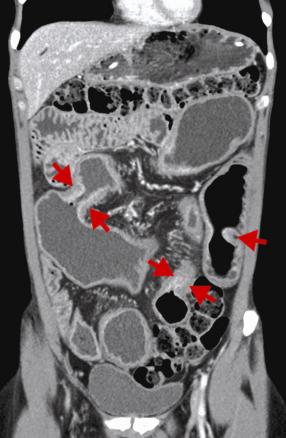

Entéroscanner, revelant une coupe coronale revelant une sténoses sévères mulitples du grêle (flèches rouges) au cours d'une maladie de crohn